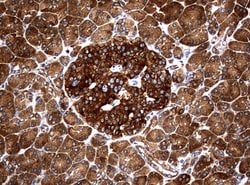

NME1 Mouse anti-Canine, Human, Rat, Clone: UMAB94, liquid, UltraMAB™

NME1 was identified because of its reduced mRNA transcript levels in highly metastatic cells. Nucleoside diphosphate kinase (NDK) exists as a hexamer composed of ′A′ (encoded by this gene) and ′B′ (encoded by NME2) isoforms. Mutations in the gene have been identified in aggressive neuroblastomas. Two transcript variants encoding different isoforms have been found for this gene. Co-transcription of this gene and the neighboring downstream gene (NME2) generates naturally-occurring transcripts (NME1-NME2), which encodes a fusion protein comprised of sequence sharing identity with each individual gene product.Specifications

| Immunocytochemistry, Immunofluorescence, Immunohistochemistry (Paraffin) | |